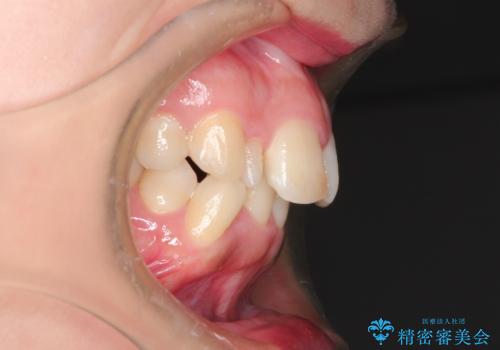

左上の犬歯が通常の位置より、かなり上方にあり、乳歯の残存と前歯のがたつきがありました。

犬歯も通常の位置にまで移動することができ、口元もすっきりすることができました。